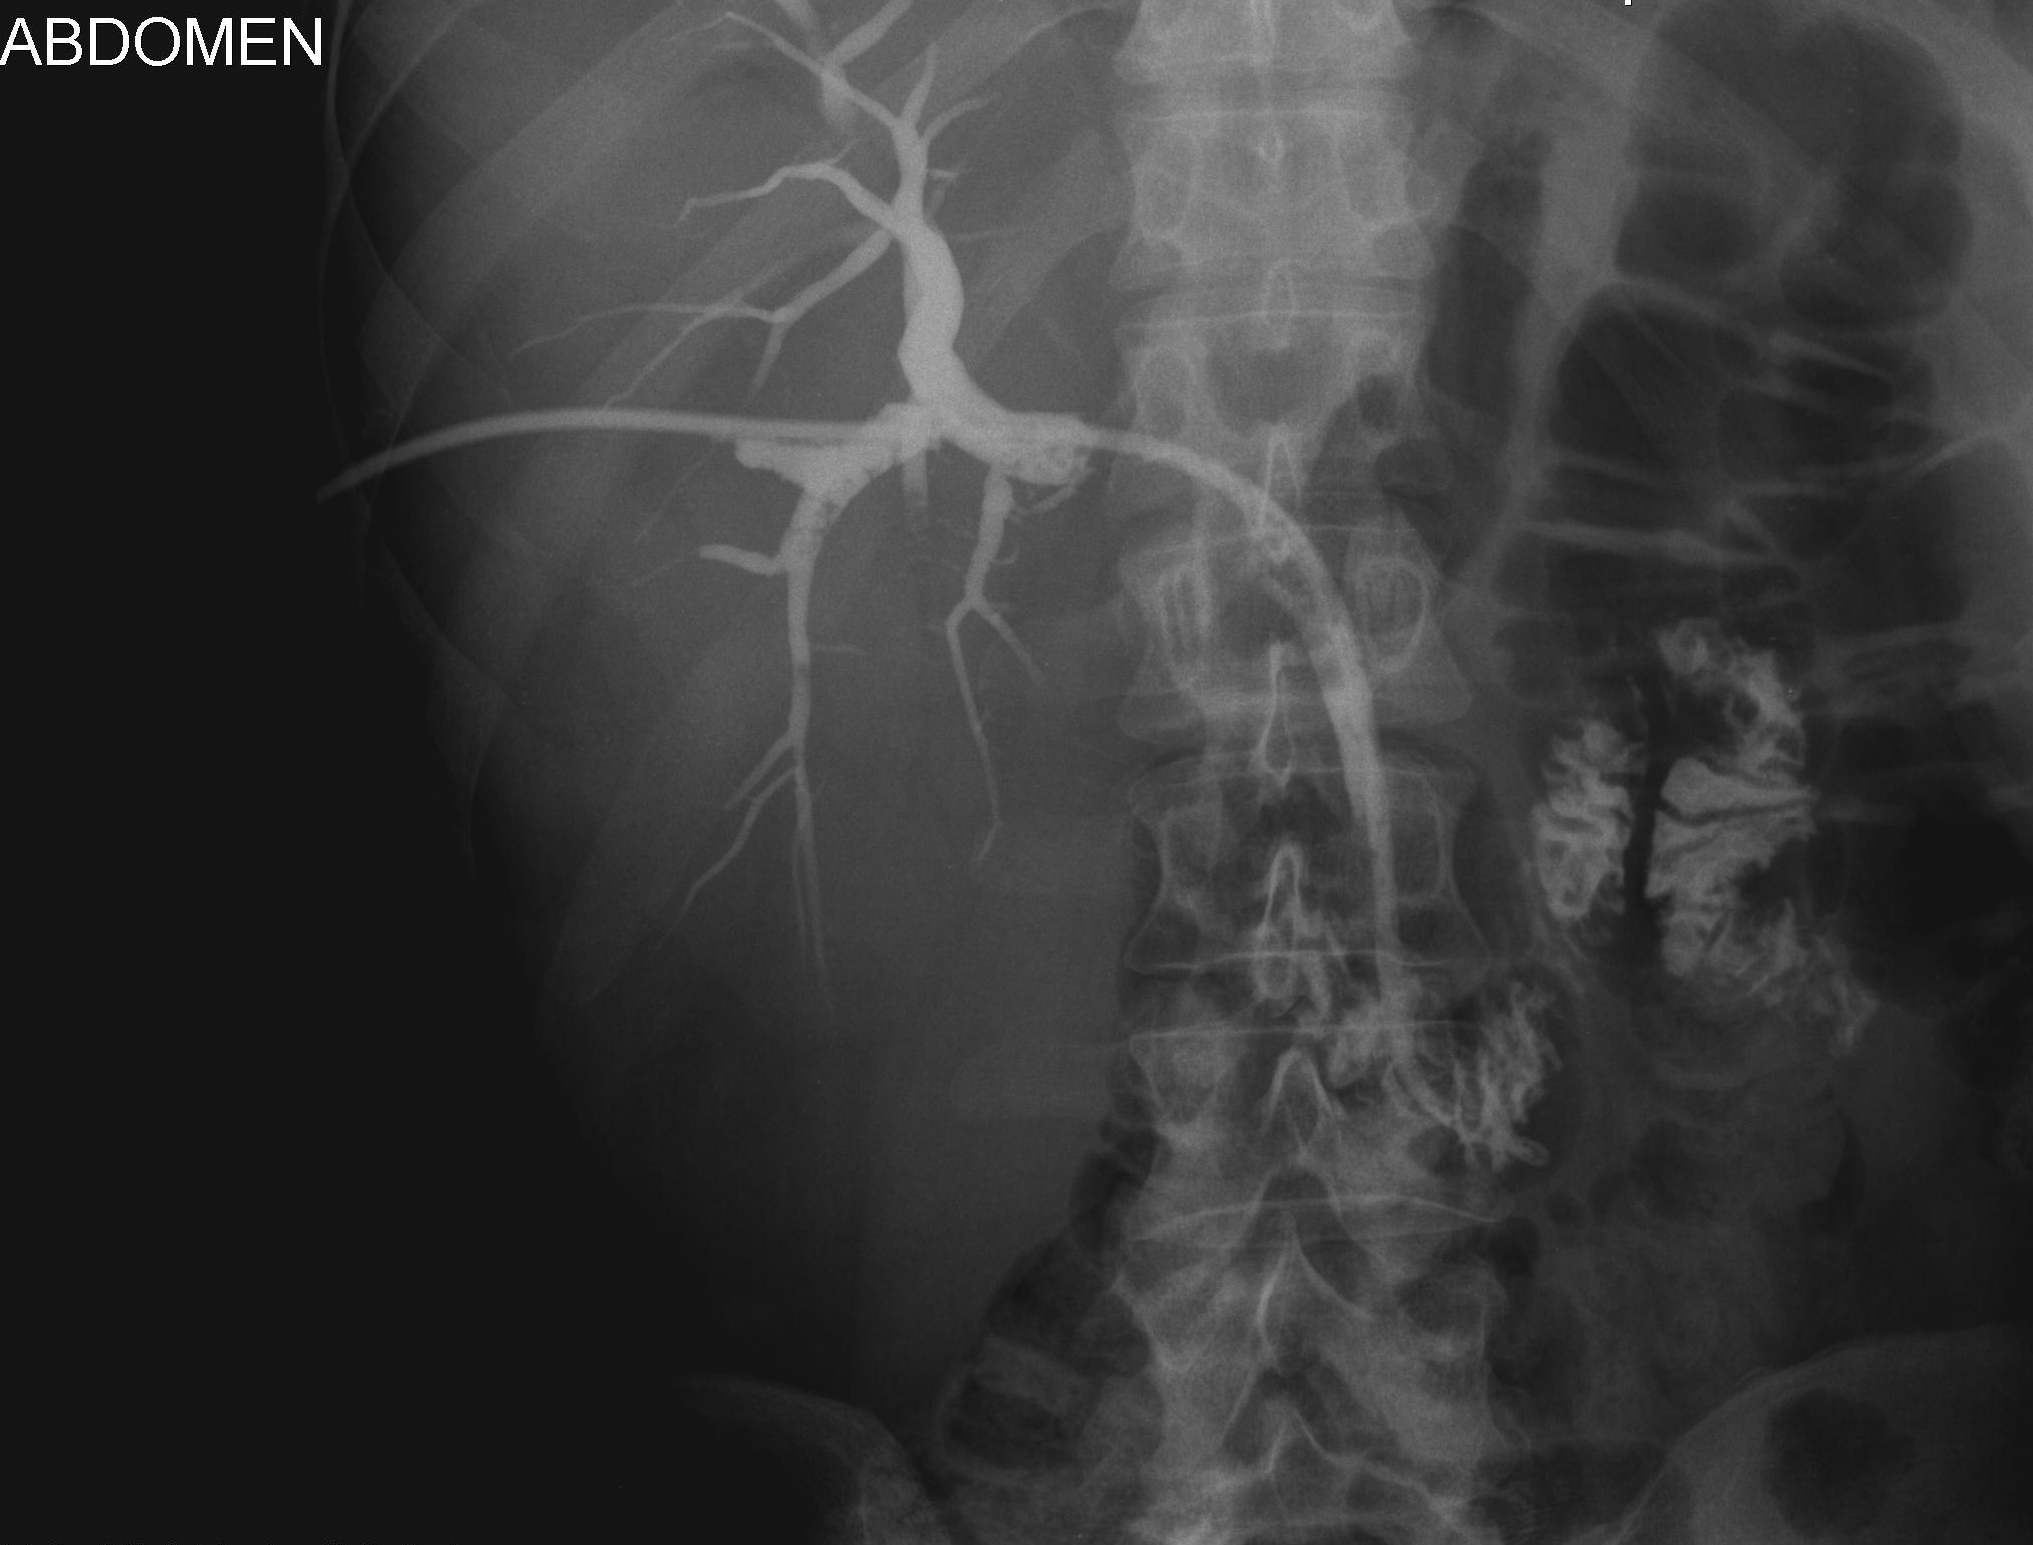

Cholangiografia - widok dróg żółciowych przed implantacją aplikatora do brachyterapii, założono dren 10 F metodą rendez-vous.